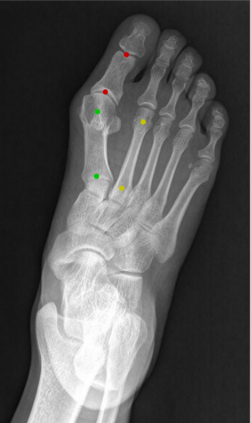

Angular measurements is essential to make a resonable treatment for Hallux valgus (HV), a common forefoot deformity. However, it still depends on manual labeling and measurement, which is time-consuming and sometimes unreliable. Automating this process is a thing of concern. However, it lack of dataset and the keypoints based method which made a great success in pose estimation is not suitable for this field.To solve the problems, we made a dataset and developed an algorithm based on deep learning and linear regression. It shows great fitting ability to the ground truth.